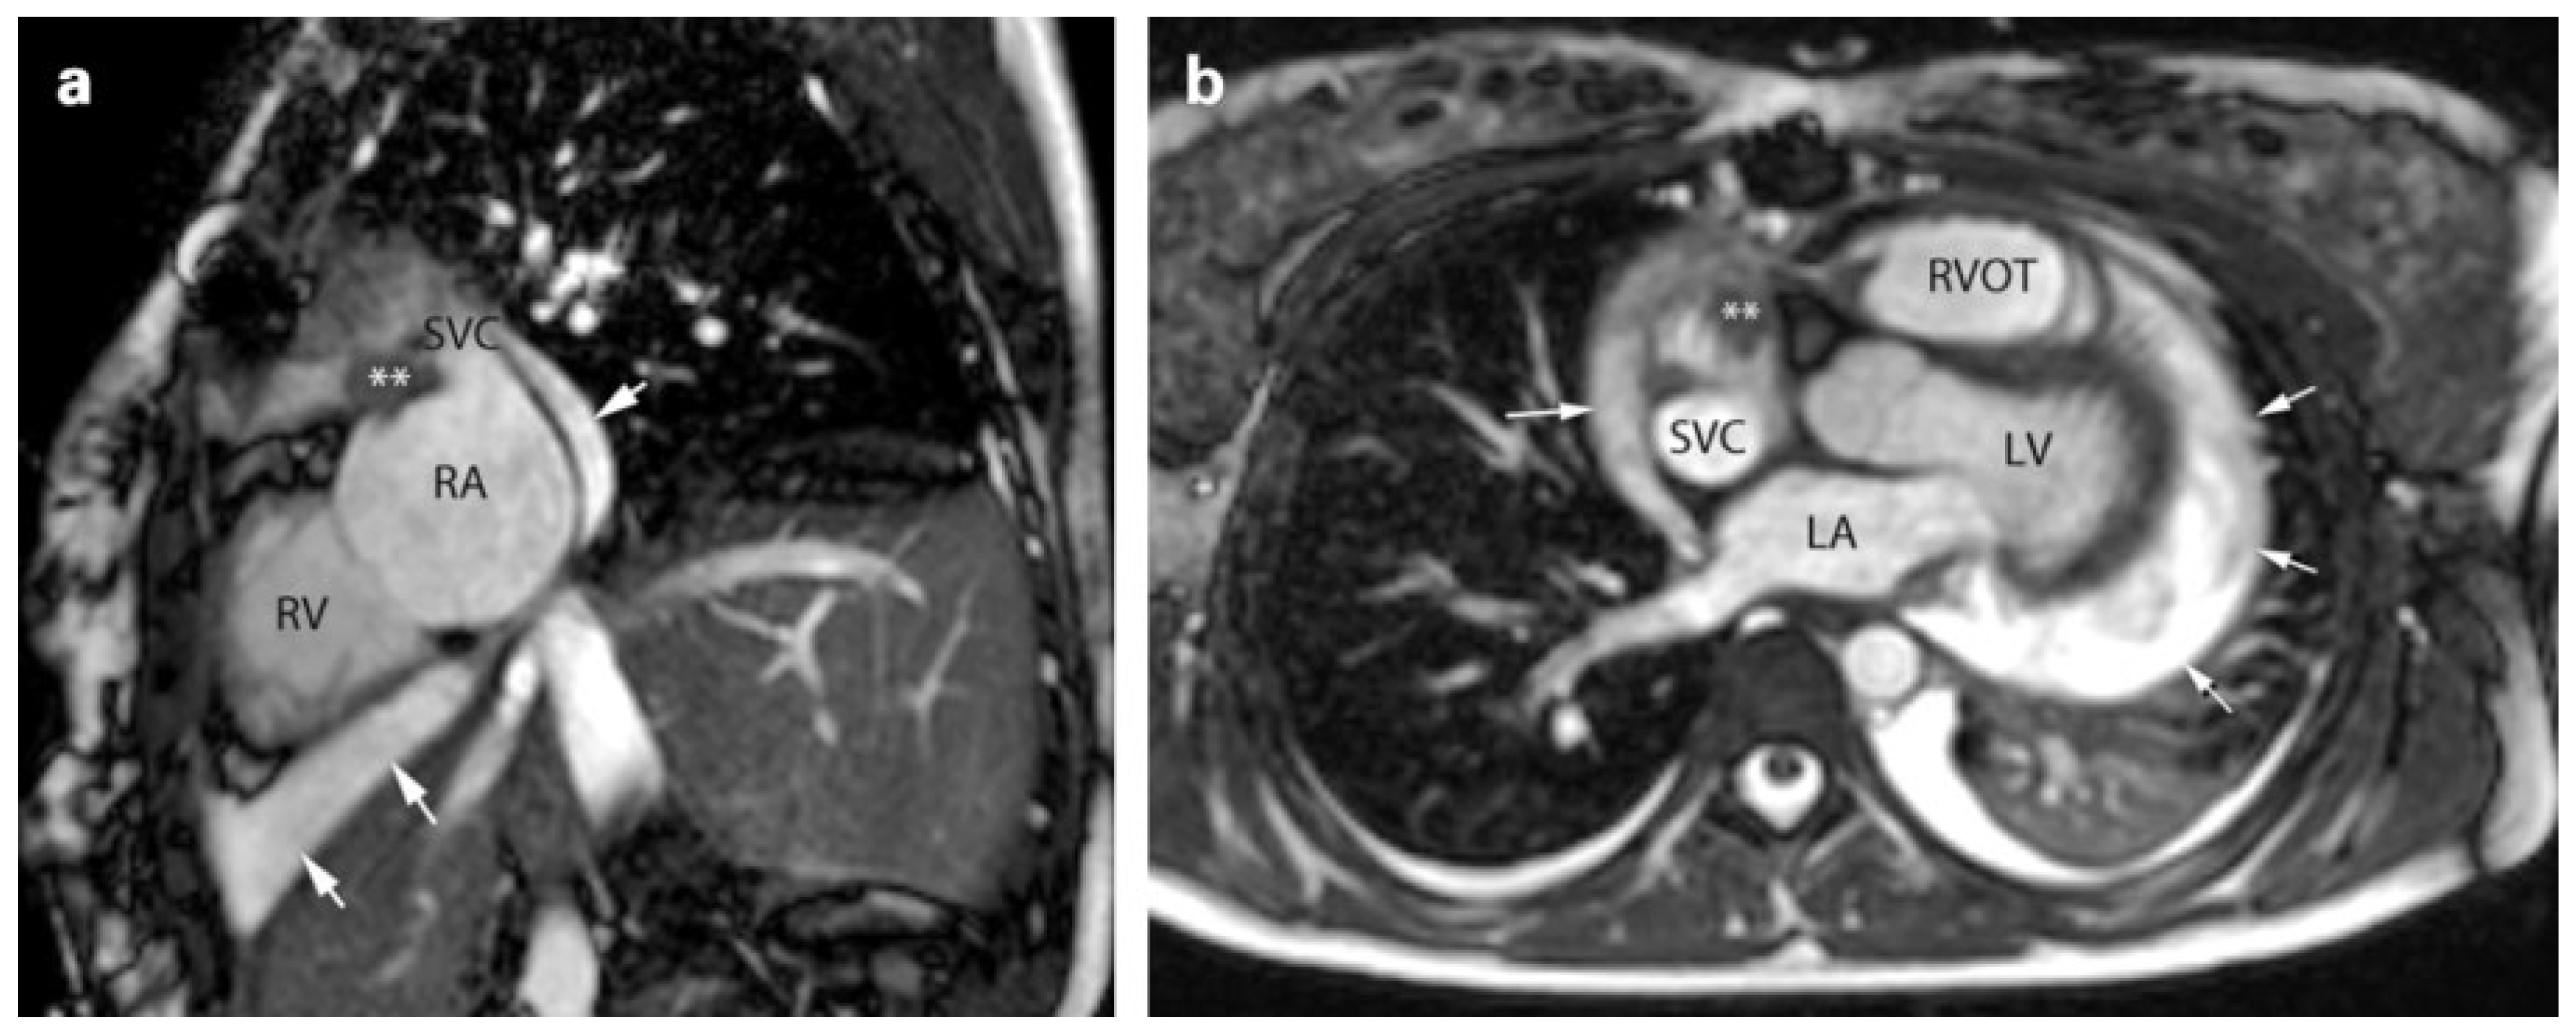

Histological workup of the frozen section showed a malignant mesenchymal tumour, and staining re-vealed an angiosarcoma (Figure 1). Whole body and cardiac magnetic resonance imaging (MRI) (Figure 2) and the analysis of peritoneal fluid taken during the first operation showed no evidence of a primary extracardiac tumour nor metastases.

Figure 2. Cardiac magnetic resonance (CMR) cine images (steady state free precession) in an axial (a) and in a short axis (b) view of the residual tumor after first resection. The mass (**) can be recognised on the back of the right atrial appendage, at the entrance of the superior vena cava. The images also show presence of pericardial effusion (arrows). LA: left atrium; RA: right atrium; RV: right ventricle; RVOT: right ventricular outflow tract; SVC: superior vena cava.

In this case, the leading symptoms were related to a massive pericardial effusion. The tumour caused a covered perforation in the right atrial wall, but was not visible in the CT scan – a known difficulty because the tumour mass and the surrounding effusion or myocardial mass may have similar densities. [7] Even MRI could barely depict the tumour (Figure 2). In our patient, the acute bleeding resulted in early detection of the tumour, which was still small and without metastases. In terms of long-term survival, this might have been life-saving.